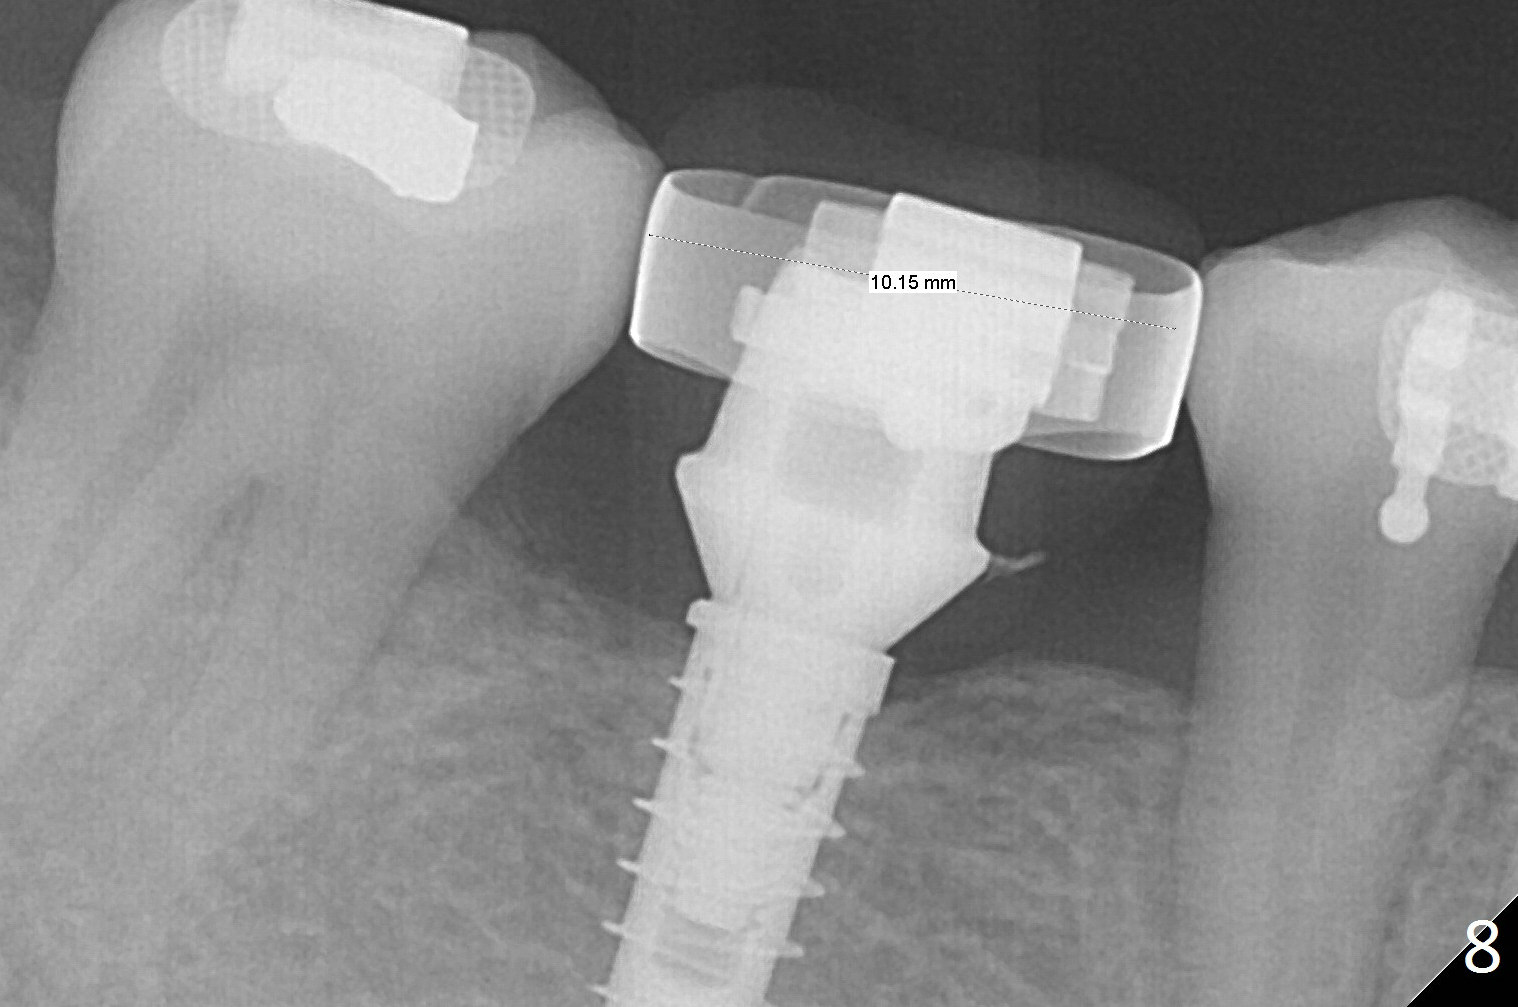

Periodontal dressing is removed ~ 1 week postop. The tooth #31 appears to rotate under the pressure of the open coil spring. One month postop, the patient will return for #30 provisional. Once the latter is being finished, add composite or new acrylic to the distal surface (if possible, more lingual than buccal) so that the tooth #31 will be distalized. The existing arch wire will be placed with or without open coil spring. A band will be placed at #30 3-4 months postop so that an open coil spring will be placed between #30 and 31. The treatment will terminate when the mesiodistal edentulous space is 9-10 mm.

A provisional is fabricated 1 month postop to prevent the tooth #31 from rotation under the tension of the open coil spring, as mentioned above. Acrylic is added distal for #31 distalization nearly 2 months postop. More definitive orthodontic action begins 3 months postop (Fig.7, banding and open coil spring). The edentulous space increases to satisfactory width 3.5 months postop (Fig.8). A normal sized crown is delivered 4 months postop (Fig.9). The patient is pleased with the new tooth (Fig.10 nearly 6 months post cementation). There is no bone loss 13 months post cementation (Fig.11 (pan), 12 (CT coronal section (L: lingual))).